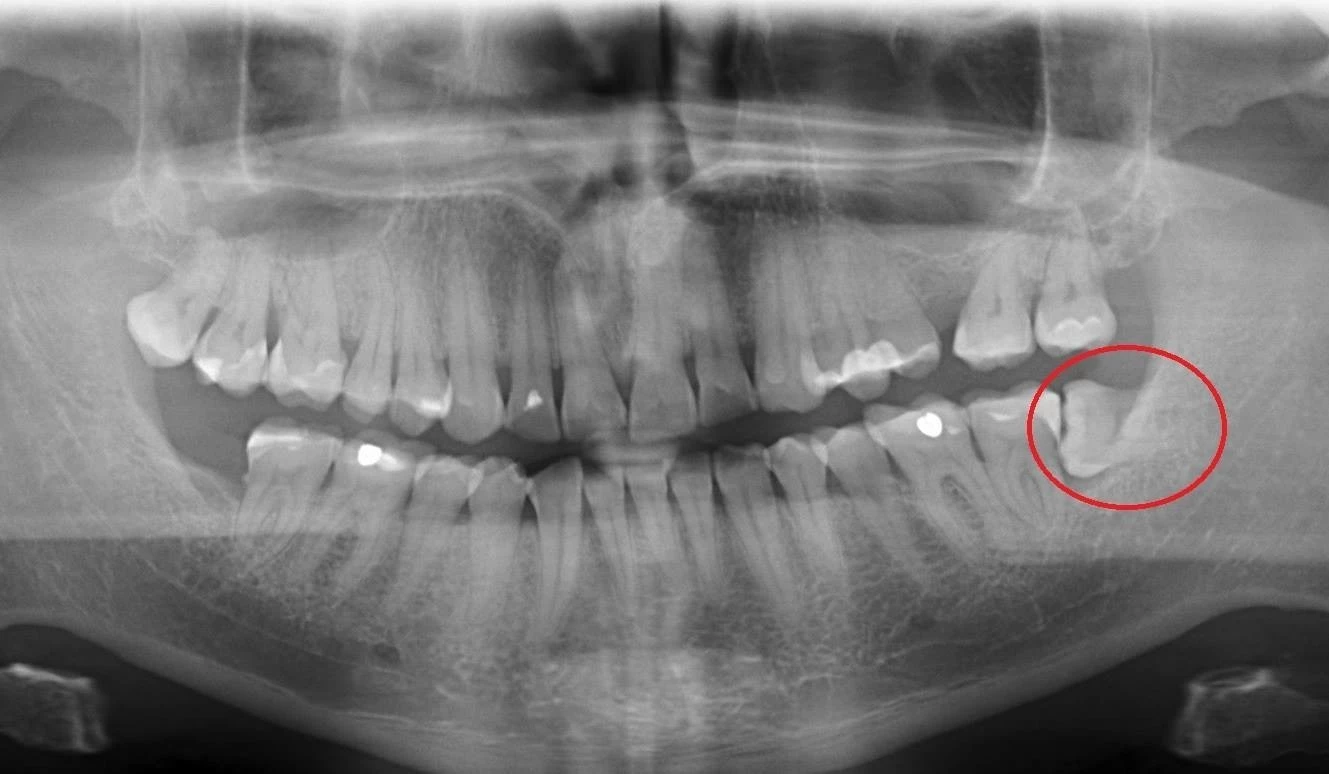

5. "półksiężycowata" kieszonka kostna poza koroną zęba na zdjęciu RTG

Poniżej przedstawiamy zabieg usunięcia zatrzymanego zęba mądrości wykonany przez specjalistę chirurgii stomatologicznej - dr Tomasza Kozioła, który polegał na znieczuleniu miejscowym, odsłonięciu zęba, zniesieniu blaszek kostnych z okolicy zęba, odcięciu korony i jej usunięciu, rozdzieleniu korzeni i ich usunięciu oraz zszyciu rany.